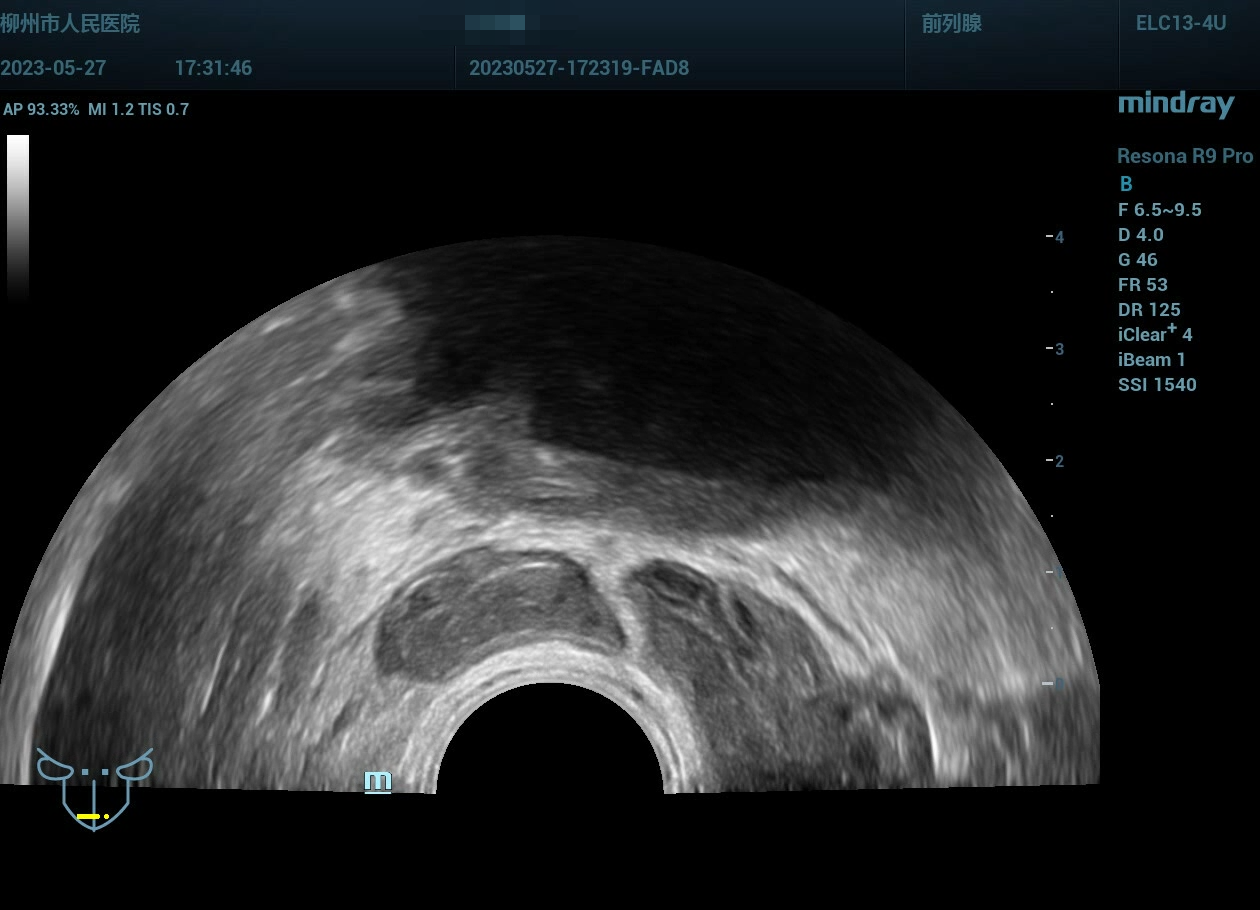

病史为年轻的男性,主要症状为尿痛、血精。

精囊腺的超声图像表现:肿胀、回声紊乱。